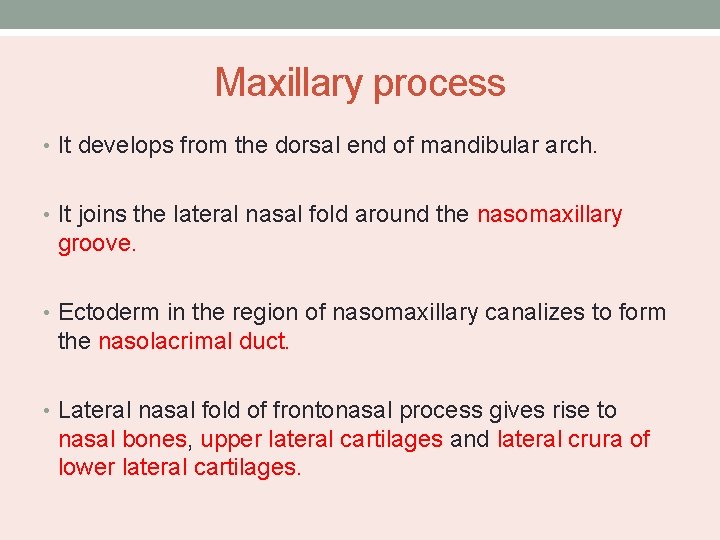

Maxillary process • It develops from the dorsal end of mandibular arch. • It joins the lateral nasal fold around the nasomaxillary groove. • Ectoderm in the region of nasomaxillary canalizes to form the nasolacrimal duct. • Lateral nasal fold of frontonasal process gives rise to nasal bones, upper lateral cartilages and lateral crura of lower lateral cartilages.